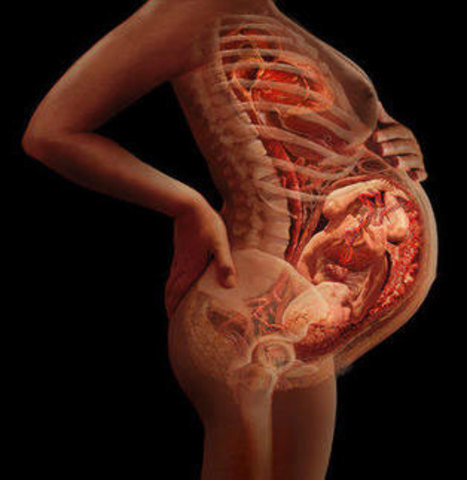

• Semana 28

Semana 28

28ª semana (7º mes): el feto pesa entre 1000 gramos y 1300 gramos. Las arrugas de la piel comienzan a desaparecer porque se deposita tejido graso debajo de la dermis. El cabello es más largo que los pelos del resto del cuerpo. Los bordes de los párpados, que estaban unidos desde el tercer mes, se separan. Los pulmones comienzan a adquirir movimientos respiratorios. El sistema nervioso central puede regular la temperatura y los movimientos respiratorios.